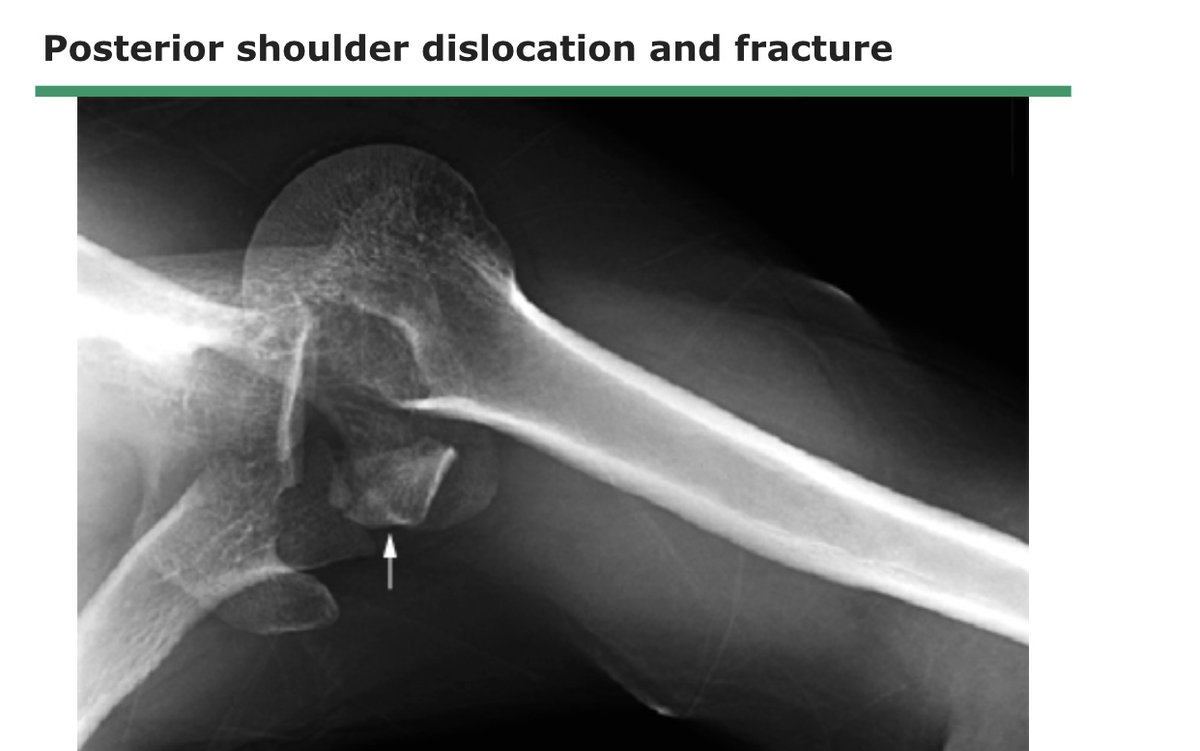

النوع الثاني :

نسبة حدوثه اقل ، طريقة الاصابة تكون في وضعية ( العضد قريبه من الجسم ، عظمة العضد ملتفه للداخل ) يحدث في حالات التشنج للجسم

العلامة المميزة له تسطح الجزء الامامي للكتف

يصاحبه غالبا كسر لرأس عظمة العضد او تهتك للغضروف او قطع وتر العضلة المدورة